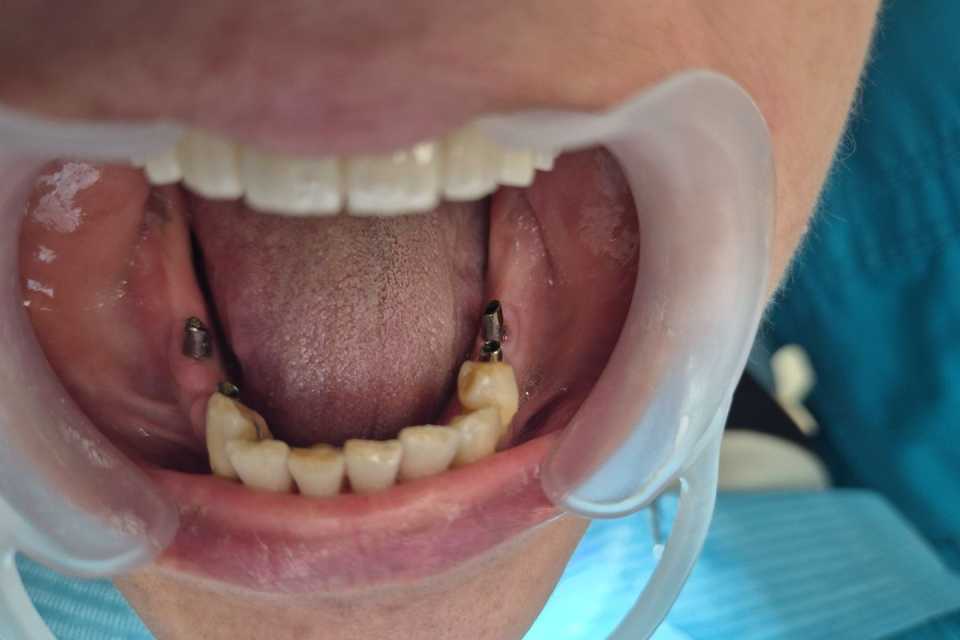

La nivelul mandibulei, reabilitarea zonelor laterale premolar-molar s-a realizat prin inserarea a câte două implanturi pe fiecare parte, protezate după 2 luni cu două lucrări din ceramică pe suport de zirconiu, cimentate. Dintii restanți ai mandibulei au fost conservați după tratamentul parodontal și solidarizați printr-o contenție linguală.